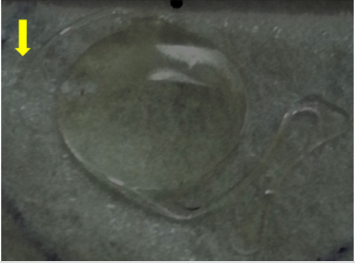

Funduscopy was unremarkable in both eyes. In order to avoid endothelial cell loss and corneal endothelial decompensation, exchange of the dislocated IOL was performed on the following day. Pilocarpin 2% eye drops were given twice daily and the patient was instructed to keep 45 degrees seating position until surgery so as to avoid dislocation of the acIOL into the vitreous cavity. The acIOL exchange was performed under subtenon’s block. After creating a 6mm-limbal tunnel incision at 12.00 limbus position, the anterior chamber was filled with viscoelastic and the acIOL was delivered with McPherson forceps. Interestingly, upon explantation of the acIOL became evident that the distal loop was fractured, and the fragment remained in the inferior angle. Subsequently, the latter was also removed and another Kelman-type acIOL (MTA3U0, Alcon, USA) was inserted into the anterior chamber and the tunnel was sutured with interrupted Nylon 10-0 sutures. The postoperative regimen included chloramphenicol/dexamethasone eye drops every three hours for the first 5 days, then 4 times a day for one week and finally twice a day for three weeks. On the first postoperative week, BCVA OD was 0.6 and intraocular pressure was 15 mmHg (Figure 2). The new acIOL was well-positioned in the anterior chamber and no iritis was present.

Figure 2: Photo of the intraocular lens fragments after explanation. Note that the fracture point is located at the proximal part of the lens loop.